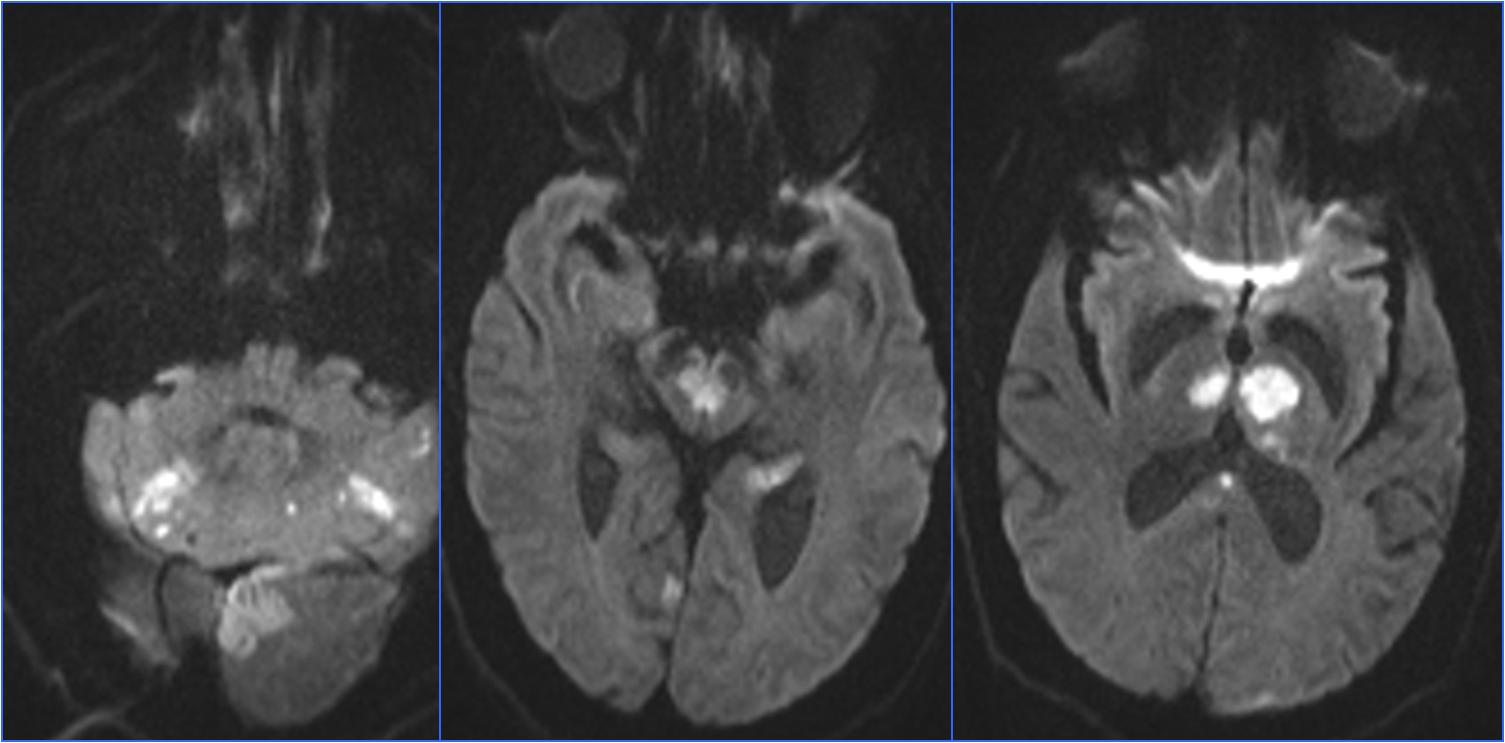

▼术前头MRA

▼术后24小时CT